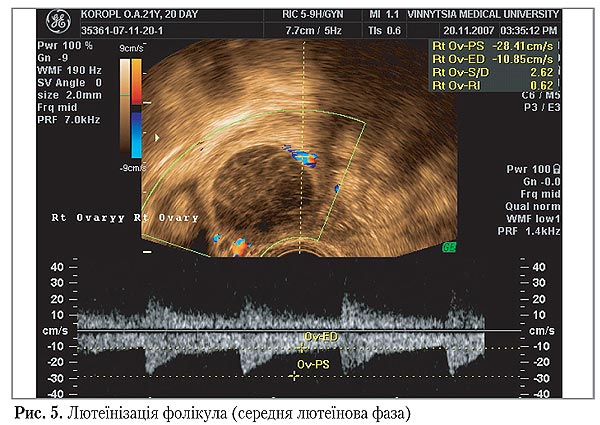

Звертає на себе увагу той факт, що більш низькі показники швидкості кровообігу та високі показники судинного опору, що визначалися в преовуляторних фолікулах ужінок з НЛФ II групи, які мали запальні захворювання в анамнезі, спостерігалися і у сформованих на їх місці жовтих тілах. У групі здорових жінок в пізню лютеїнову фазу спостерігалося поступове підвищення величин індексів резистентності, яке відповідало фізіологічному регрессу жовтого тіла і не перевищувало 0,52–0,54. У жінок з НЛФ показники периферичного судинного опору були стабільно високими протягом ранньої, середньої та пізньої лютеїнової фази і, в середньому, становили 0,56–0,58. Також було відмічено, що при досягненні преовуляторним фолікулом розмірів 24 мм і більше у жінок з НЛФ спостерігався стан лютеїнізації фолікула (рис. 5).

Оцінка показників кровообігу в судинах стінки фолікулів виявила відсутність прискорення швидкості кровотоку в них напередодні овуляції, а також високі показники судинного опору — 0,62.